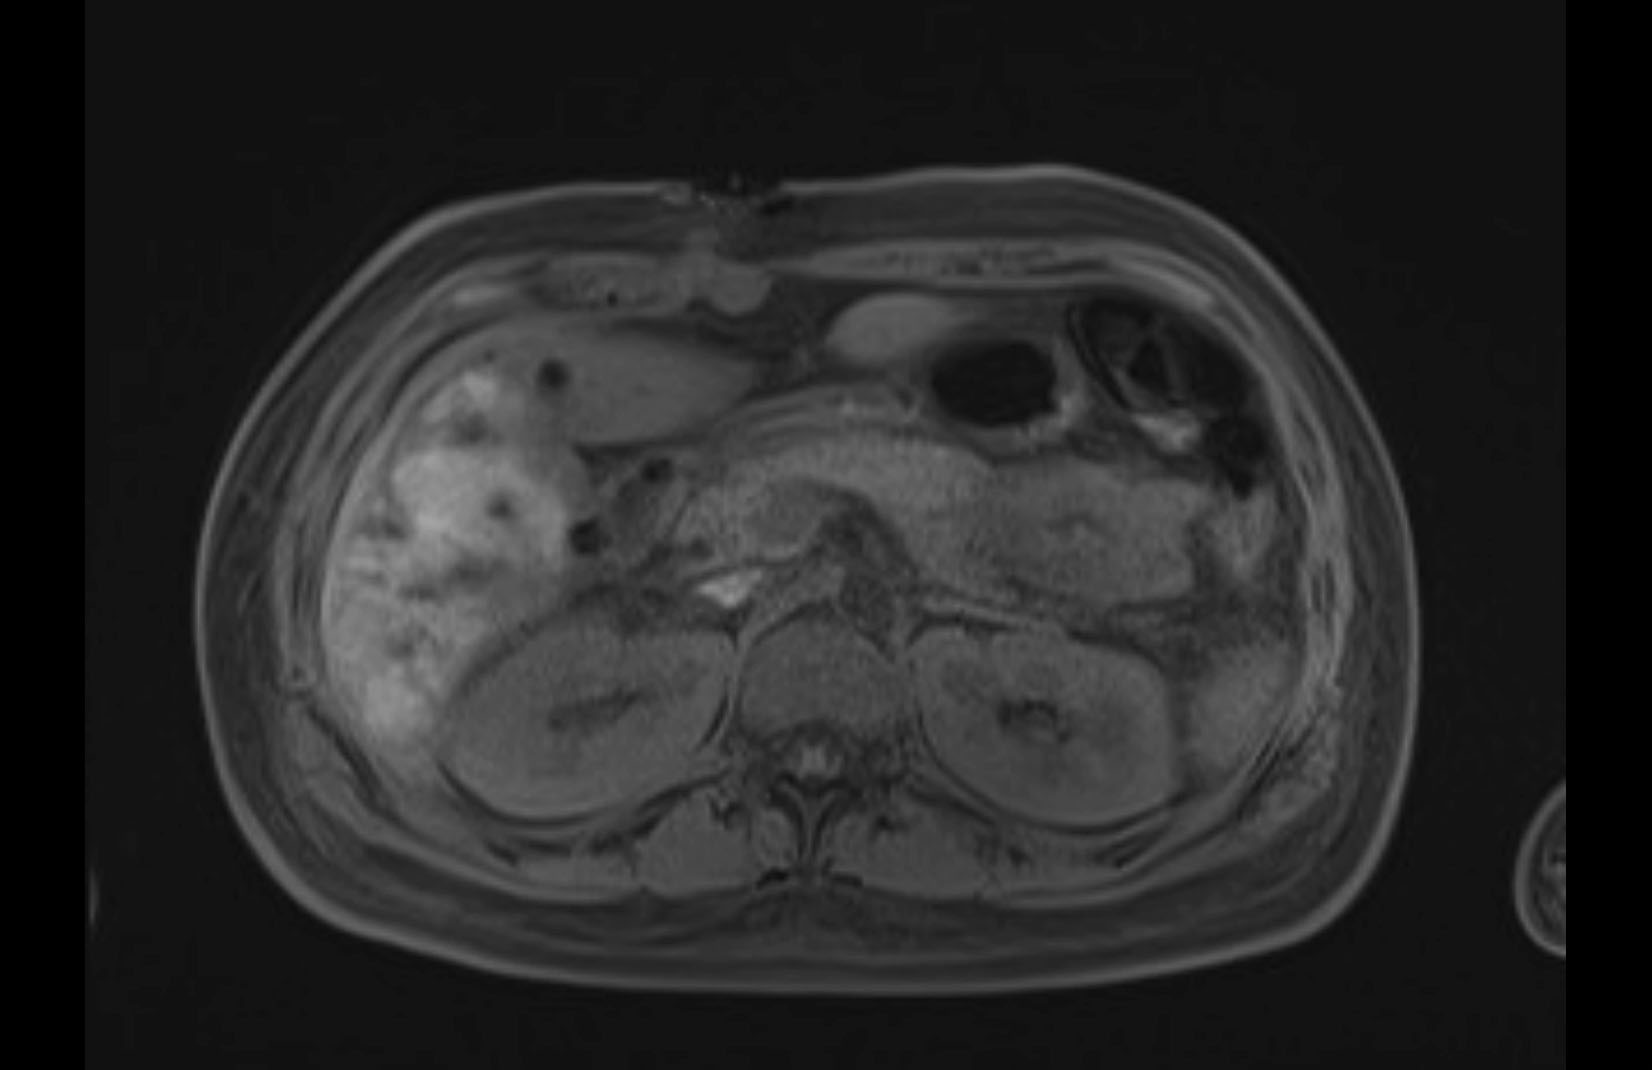

MRI T1

Imaging analysis

Based on initial findings, which issue(s) would you be most concerned about?